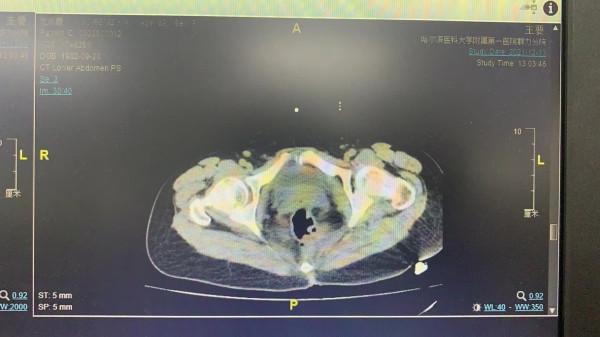

伊鐵忠教授為患者進行詳細查體、完善全面檢查後,建議手術治療。為充分評估病情,降低術中併發症,術前請泌尿外科會診,完善膀胱鏡檢查,考慮膀胱佔位病灶。術前完善盆腹腔CT檢查,提示盆腹腔多部位病灶,累及膀胱、盆腔器官,前腹壁、臍周。在完善術前檢查後,經多學科會診,在國家二級教授鄭建華專家指導下,決定給予開腹手術治療。